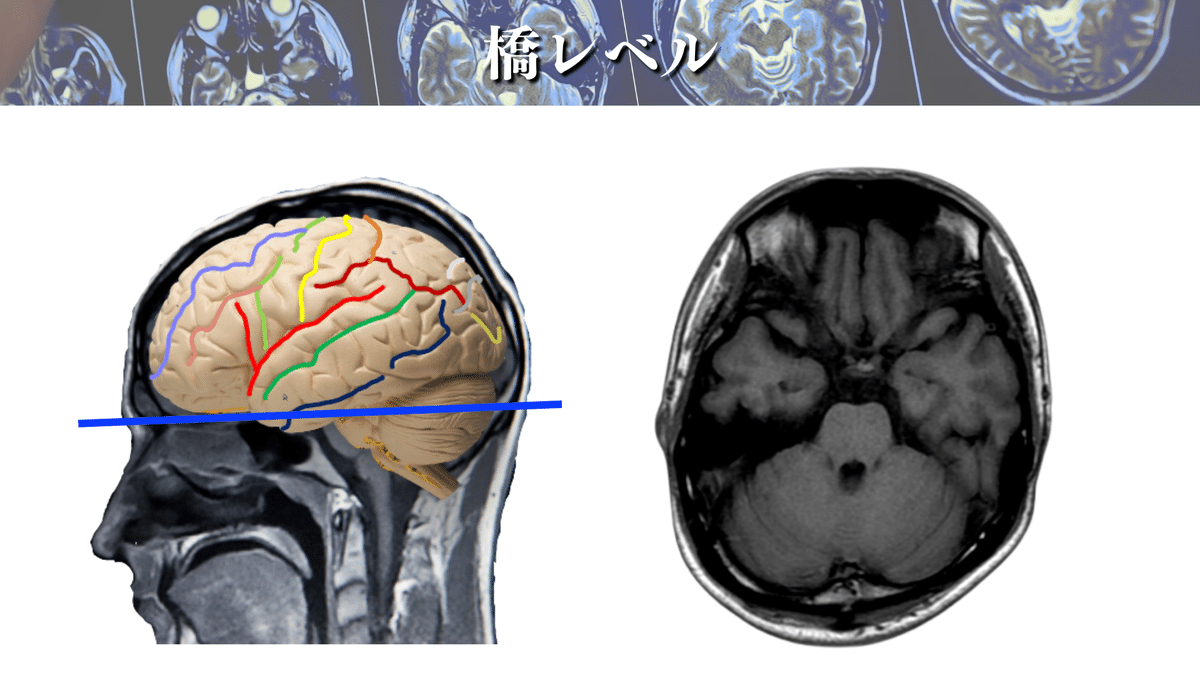

橋レベル

では、さっそく解像度を上げた画像を見てみましょう🔍

CSTは前方(橋底部)を通過しているのが分かりますね👀

橋のレベルは他の脳幹とは少し性質が異なり、右図のようにCSTが分散します!

橋では主に前方(橋底部)を走行すると覚えるといいかもしれませんね☝️